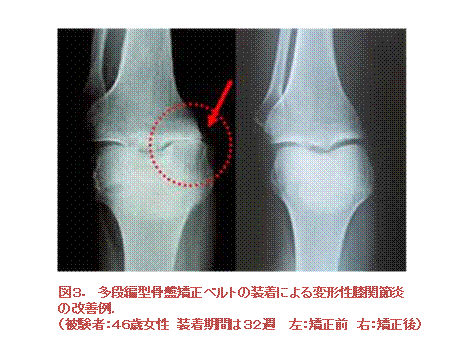

多段編骨盤矯正ベルトの装着による、一時性変形性関節症(OA)の改善への効果を検討した。

しかし、約6か月を超える多段編骨盤矯正ベルトの装着によって、滑膜中の1L-1βの濃度は有意に減少した。

多段編骨盤矯正ベルトの装着は滑膜中の1L-1βの濃度を減少させる。

このことから、多段編骨盤矯正ベルトの装着は、OAの病因および進行防止に重要な役割を果たしている可能性がある。